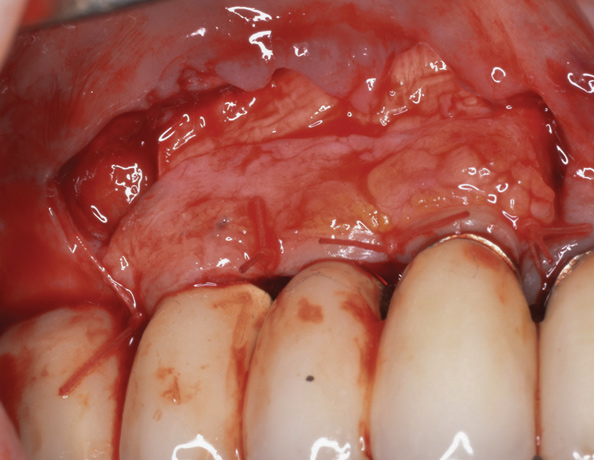

(16.) Following flap reflection, the buccal bone deficiencies are evident.

Figure 16

It is important to point out that not all implants presenting with mucogingival or esthetic complications require explantation, especially when the affected implants are partially supporting a multiple-unit restoration. This can be demonstrated in the following case. Implants were placed almost 20 years prior to the patient presenting with advanced soft-tissue recession on the maxillary right arch (Figure 15). There was a lack of keratinized/attached mucosa and buccal bone deficiency. This bone deficiency was not pathologic, but the result of physiologic remodeling,6 which was evident following flap reflection (Figure 16). At the time that these implants were placed, simultaneous bone augmentation to offset the diminution of the arch after tooth extractions was not a prerequisite.7 Also, the importance of soft-tissue augmentation at the time of immediate implant placement was not fully appreciated when this patient was originally treated.8,9 Formation of biologic width combined with a thin periodontal biotype often results in significant crestal bone loss.10 More recently, the importance of increasing soft-tissue thickness as it relates to more favorable crestal bone preservation has been demonstrated by Linkevicius and colleagues.11 Removing these implants would commit the patient to remaking her large prosthesis; therefore, she was interested in maintaining them with a corrective mucogingival procedure.

After gentle debridement with glycine air abrasion and sterile saline, a cross-linked, porcine collagen bone matrix (OSSIX® VOLUMAX; Datum Dental Ltd.) was placed over the buccal aspect of all three affected implants (Figure 17). Next, a subepithelial, connective tissue graft harvested from the right aspect of the patient's hard palate was affixed over the bone scaffold and exposed implants and abutments (Figure 18). And finally, a coronally advanced flap was sutured over the hard- and soft-tissue grafts. The 1-month, follow-up photograph demonstrates incomplete, but significant coverage of the previously exposed implants and abutments (Figure 19).